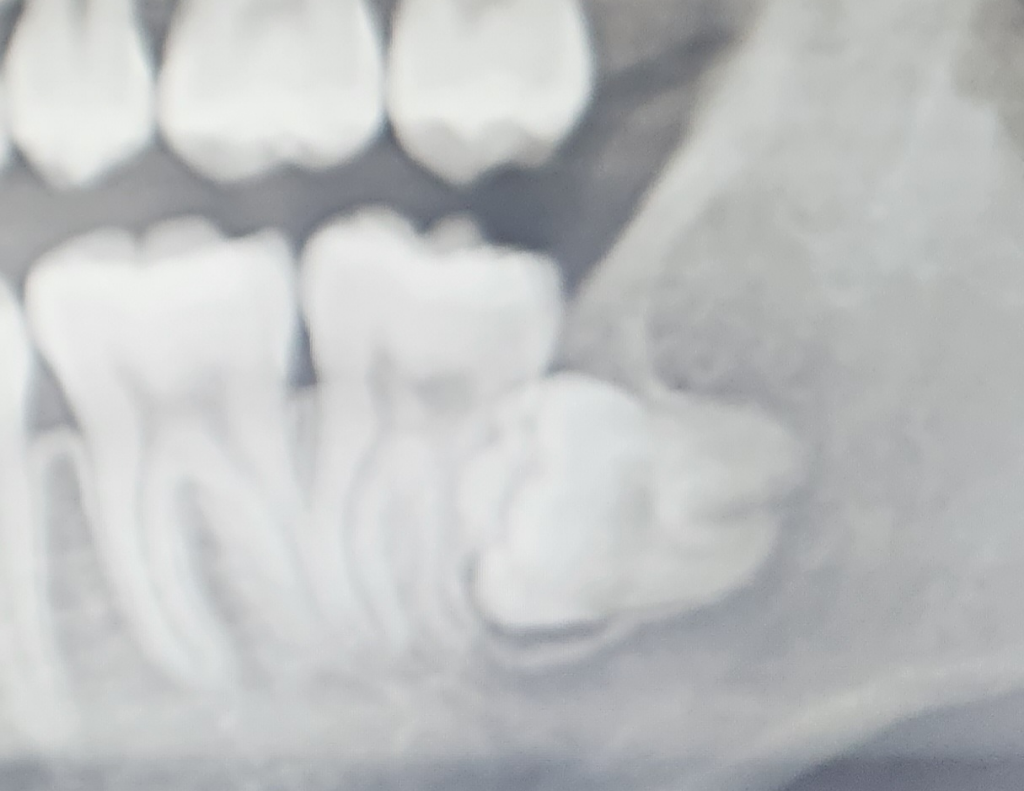

수평매복사랑니 현재 발치해야 하나요?

안녕하세요. 현 상태에서 수평매복사랑니를 발치해야 하는지 고민이 있어요.

현재 앞어금니 뿌리를 건드려서 어금니 뿌리가 꺾여있는 상태이고, 발치하게 되면 어금니가 흔들릴 수 있는 얘기를 들었어요.

사랑니가 앞의 치아 뿌리에 닿아 있기는 하지만 흡수를 하고 있는것처럼 보이지는 않아요.

1. 앞 어금이 뿌리흡수는 사랑니 머리가 닿아있어 이미 진행되고 있을 가능성이 높습니다

2. 맹출력이 남아있다하더라도 머리가 걸려있기(locking) 때문에 이 상태에서 더 나오지는 않겠습니다

현재 상태로 봐서는 신경관과의 거리도 근접해 있기 때문에 ct를 찍어봐야하고 온전히 뽑기 어려운 케이스 일수도 있습니다 뿌리를 뼈 속에 조금 남기고 앞 어금니를 밀고 있는 머리만 뽑을수도 있습니다

완전매복이기 때문에 현상태로 두면 잇몸이 붓거나 염증이 생길 확률 또는 아플확률은 높지는 않습니다 다만 옆 어금니 뿌리흡수는 진행될 확률이 높습니다